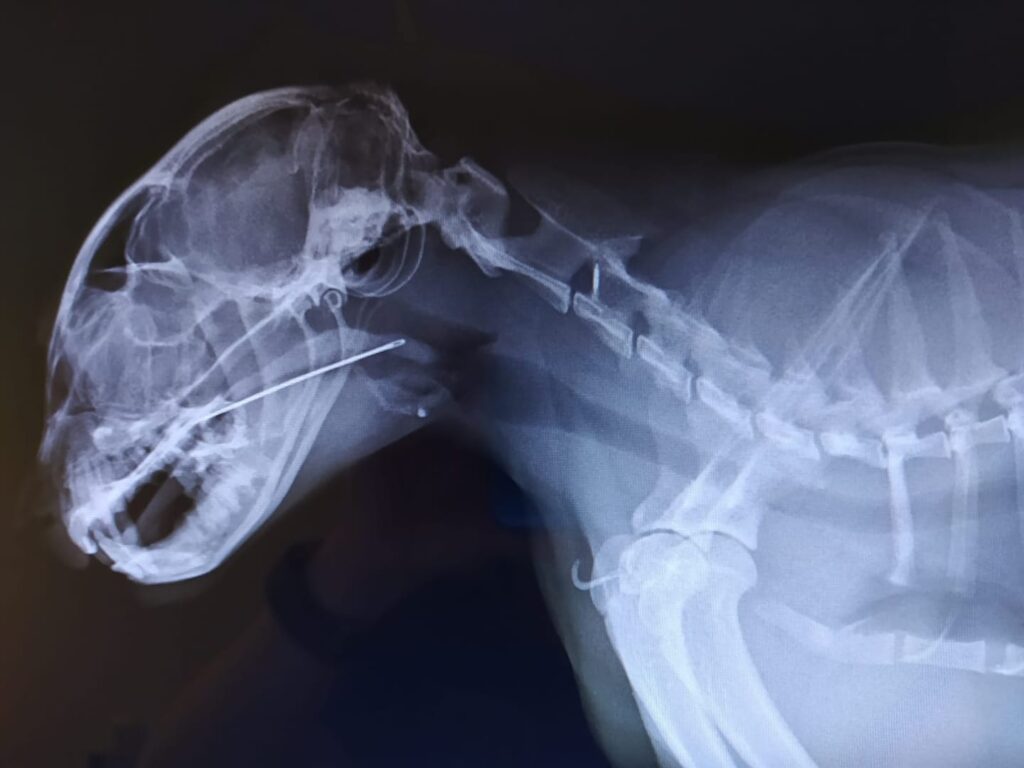

Von Ralph Rückert, Tierarzt Ein Kommentar auf Facebook: „Ganz sicher zahle ich für Wissen, Erfahrung und Sicherheit gerne mehr. Was ich mich frage ist, wieso Diagnosen heute mit unzähligen verschiedenen Geräten gestellt werden müssen, dazu noch Laborwerte. Geht diagnostizieren heutzutage nicht mehr, ohne etliche Geräte hinzuzuziehen? Und wenn, warum ist das so?“ Das ist eine […]